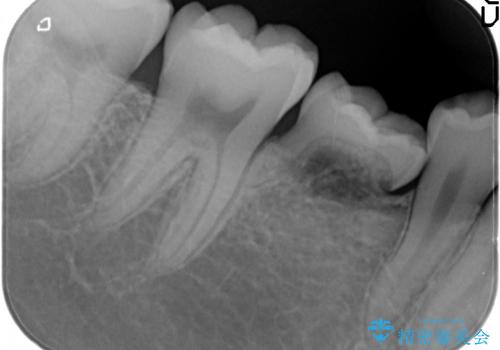

元々乳歯が残っており、永久歯が欠損していました。

また、一番後ろの永久歯(7番目)の周りに骨がたくさんあり、そこの骨の形を整えて削ってあげたほうが、7番目の歯がしっかり歯茎の炎症も治りやすい状況でした。

そのため、5番目のインプラントと、7番目の骨整形を同時に行い、整形で取れた7番目の骨をインプラント周囲に移植し、骨を増やすことにしました。

元々乳歯が残っていた場所であり、骨はたくさんあったため、インプラントを入れるのにそこまで支障はありませんでした。